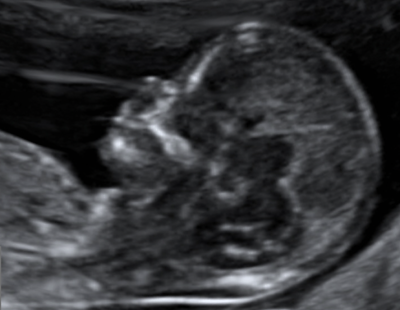

Échographie du premier trimestre

Cet examen, également appelé "échographie de datation" est effectué entre la 11e et la 14e semaine.

Il permet de :

• Voir que votre grossesse évolue favorablement.

• Confirmer le terme de votre grossesse.

• Faire un premier examen de l’anatomie de votre fœtus.

• Procéder au dépistage de certaines anomalies chromosomiques.

• Réaliser le dépistage de la pré-éclampsie.